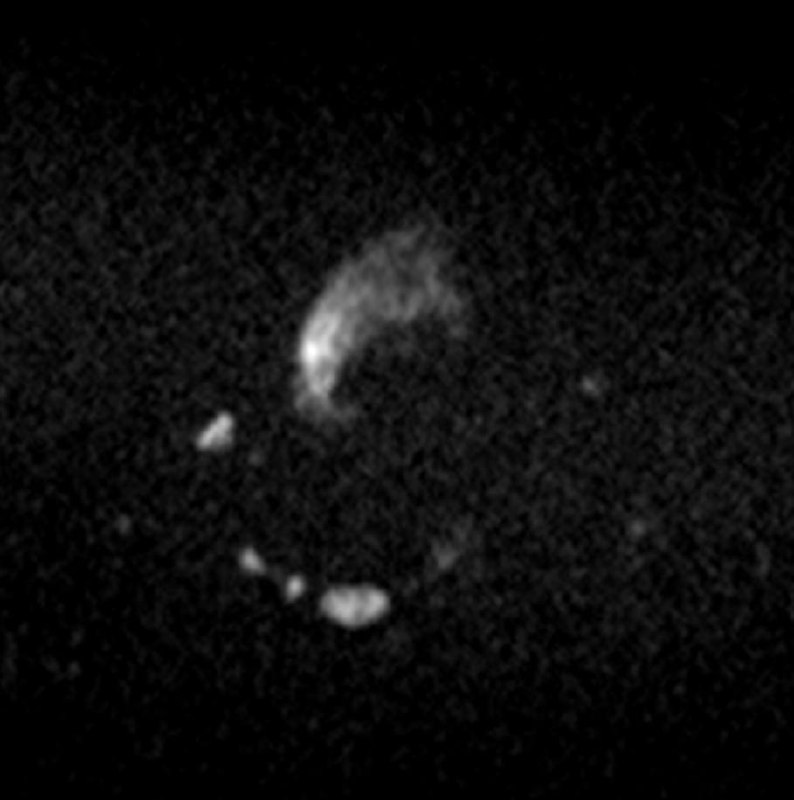

Всем привет!

А вот для чего иногда нужен контраст на МРТ предстательной железы: по DWI, а она является основной последовательностью для оценки периферической зоны, типичные изменения ПИРАЦ-4 (наибольший размер - 12 мм), но вот на Т2 - жидкость, а не серость, и на постконтрастных накопления контраста нет вообще. Так что, это - абсцесс, а не рак.

Соблюдайте протокол и не будете разочарованы.